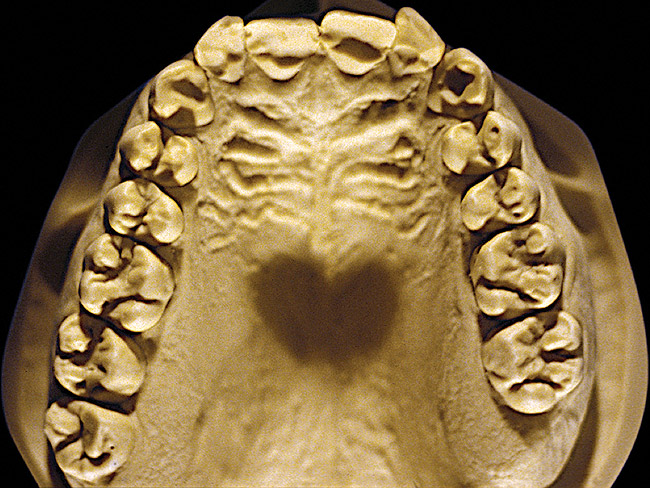

Figure 7 and Figure 8 are examples of NCLTS resulting from toothpaste. Upon examination, one could see that the overall anatomical detail of the teeth was faded with a sandblasted appearance. A closer view of the facial surfaces (Figure 9 and Figure 10) illustrates this to a greater degree and one can observe that the normal intricate facial anatomy was completely missing. It is interesting to note there was no cervical recession of the gingiva, even though every surface of every tooth had been abraded. This is due to the fact that this patient had always used a soft, round-ended filament toothbrush.21-22 This patient's sole desire regarding her oral hygiene was to get her teeth whiter.

Figure 7  Moderate NCLTS from toothpaste, maxillary arch.

Figure 7

Figure 8  Moderate NCLTS from toothpaste, mandibular arch.

Figure 8